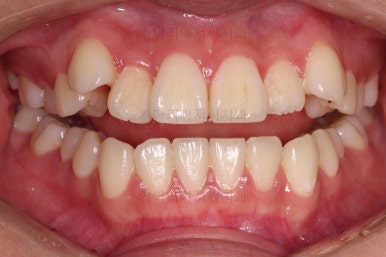

매우 급속도로 가지런해지고 있죠?

대신에 초기 단계에서는 가지런하게 하는데만 초점을 맞추게 되는데 앞니가 뻗치거나 송곳니가 양옆으로 벌어져 보이는 양상을 보입니다.

이제부터는 미니스크류를 이용해서 치열을 뒤로 잡아당겨 주면서 뻗침이나 벌어져 보이는 형태를 개선해 줍니다.

점점 느낌이 좋아지는 걸 볼 수 있죠?